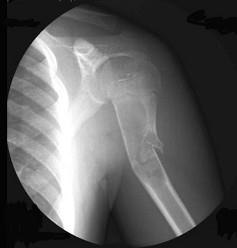

问题 5岁男性患者,外伤后致使左肩关节疼痛伴关节活动障碍1小时,X线检查如图所示,最可能的诊断是 ( )

选项 A、左肱骨上段嗜酸性肉芽肿伴病理性骨折 B、肱骨上段骨肉瘤伴病理性骨折 C、肱骨骨纤伴病理性骨折 D、肱骨上段骨囊肿伴病理性骨折 E、左肱骨上段骨折

答案 D